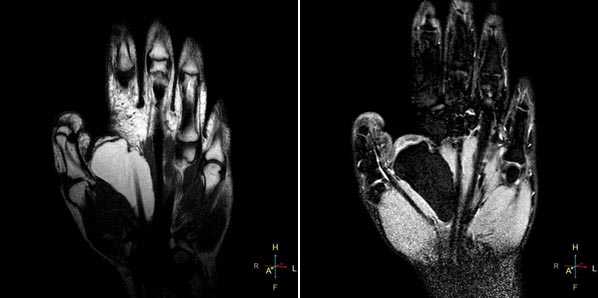

Начнем с МР-диагностики травматических повреждений кисти и лучезапястного сустава.

При клиническом обследовании больных с ушибами лучезапястного сустава и кисти, как правило, определяются болезненность при пальпации, увеличение объема окружающих мягких тканей, а объективно и рентгенологически изменения отсутствуют. Наиболее часто встречаются ушибы метаэпифиза лучевой и локтевой костей, а также полулунной и ладьевидной костей. Ушибы (контузионные поражения) кисти определяются только при МРТ-исследовании, особенно хорошо видно на программах с подавлением сигнала от жира. Морфологически ушиб кости проявляется нарушением целостности трабекул костной ткани с кровоизлиянием и отеком костного мозга. Однако, несмотря на повреждение трабекул костной ткани, рентгенологические исследования, включая КТ, не позволяют обнаружить патологические изменения.

Клинические проявления у пациента: боль и ограничение движений после падения на вытянутую руку 4 месяца назад.